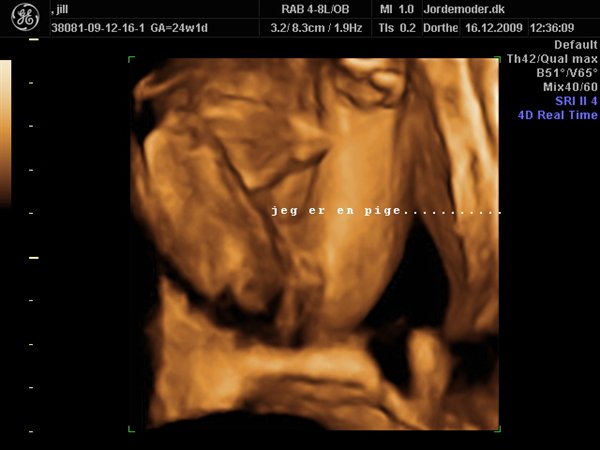

jillkolsbjerg

her er vores prinsesse......håber der går nogle år før hun spreder ben sådan igen når hun er kommet ud

knus jill 32+3

Vedhæftede fotos (klik for at se i fuld størrelse)